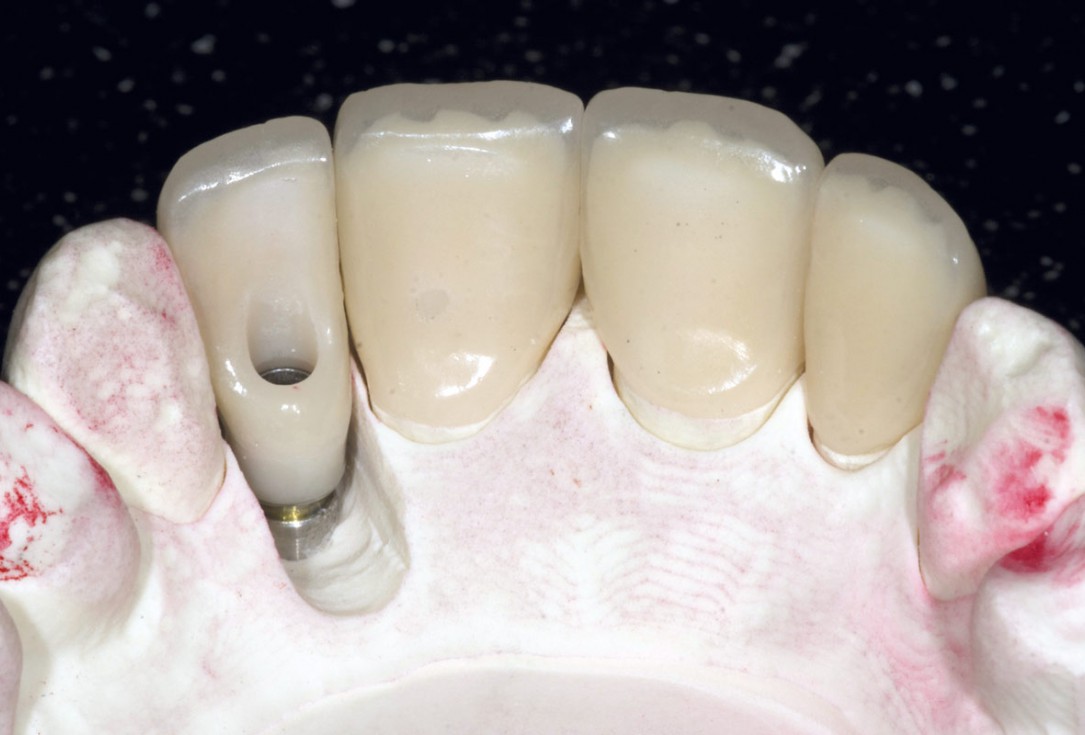

15/19 - Screw retained final implant prosthesis and adjacent ceramic unitsBone augementation with maxresorb® - Dr. R. Cutts